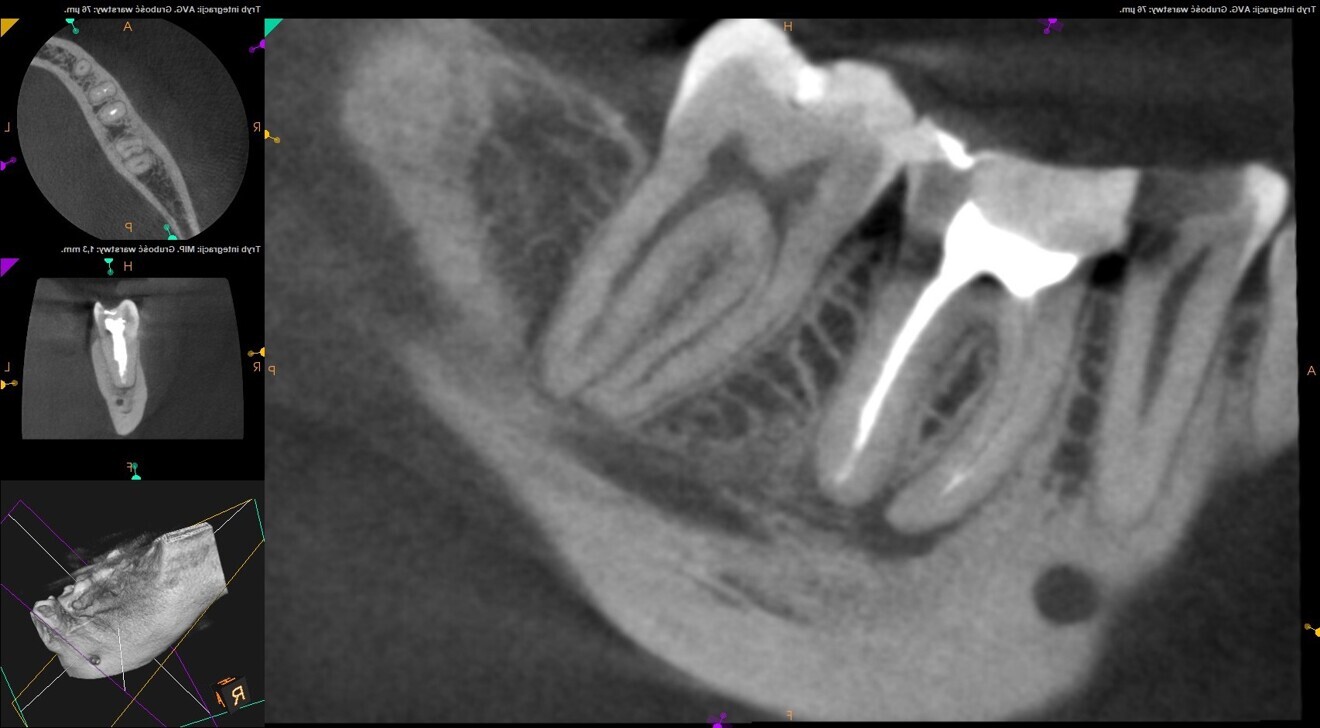

Fig. 2: Pre-op CBCT scan. Broken file far beyond the canal curvature.

Fig. 3: Pre-op CBCT scan. Tip of the broken file located below the junction of the mesiobuccal and mesiolingual canals.

The periapical radiograph and the CBCT scan revealed that the file had broken far beyond the curvature in the mesiobuccal canal and below the junction with the mesiolingual canal. Also, a periapical lesion was visible around the apices of the mesial and distal roots (Figs. 1–3). The length of the file was approximately 5 mm. Bypassing the file through the mesiolingual canal would have been a risky procedure because it may have caused the fracture of the second instrument and the obturation may also have been very challenging. Thanks to SWEEPS technology and a bioceramic sealer, an alternative approach could be taken. After administering anaesthesia and placing a dental dam, the temporary restoration was removed (Figs. 4 & 5). The pulp chamber was rinsed with 5.25% sodium hypochlorite and the irrigant activated with ultrasonics. After cleaning the chamber of the tooth, the dental dam and clamp were rinsed with water and dried and flowable dental dam was placed to seal the tooth and enlarge the space in the pulp chamber for the laser-activated irrigation (Fig. 6). Activation was performed with the SkyPulse laser (Fotona). The AutoSWEEPS mode was chosen. The power of activation was set to 1 W. The flat SWEEPS 300/20 fibre tip was used (Fig. 7). The tip was placed slightly below the orifice of the mesiobuccal canal for the majority of the irrigation with sodium hypochlorite. After 120 seconds of activation with sodium hypochlorite, the tip was placed in the pulp chamber to activate the sodium hypochlorite in all the canals simultaneously for 30 seconds. This procedure was continued for 30 minutes. Only the distal canal was shaped with rotary files, up to size 40/.04. Both mesial canals remained the same size as they were before the file broke during the primary treatment. Finally, the canals were flushed with EDTA activated with AutoSWEEPS at a power of 0.4 W, and sodium hypochlorite was activated for three cycles with AutoSWEEPS at a power of 0.6 W and with a 30-second break for the resting phase. The irrigant flow between the mesiobuccal and mesiolingual canals was rapid, indicating that obturation could be performed.